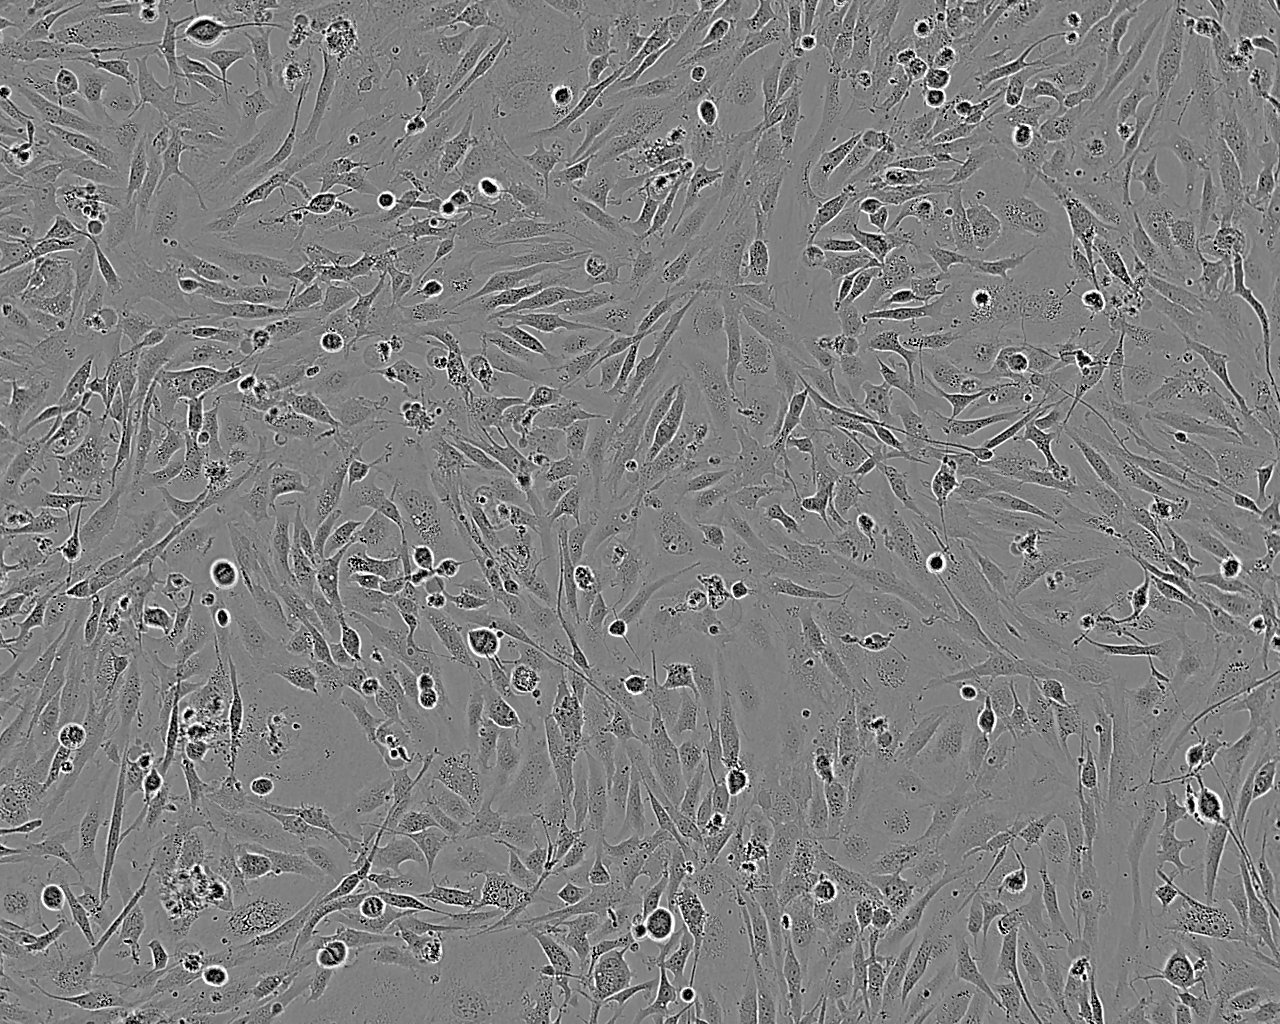

Images